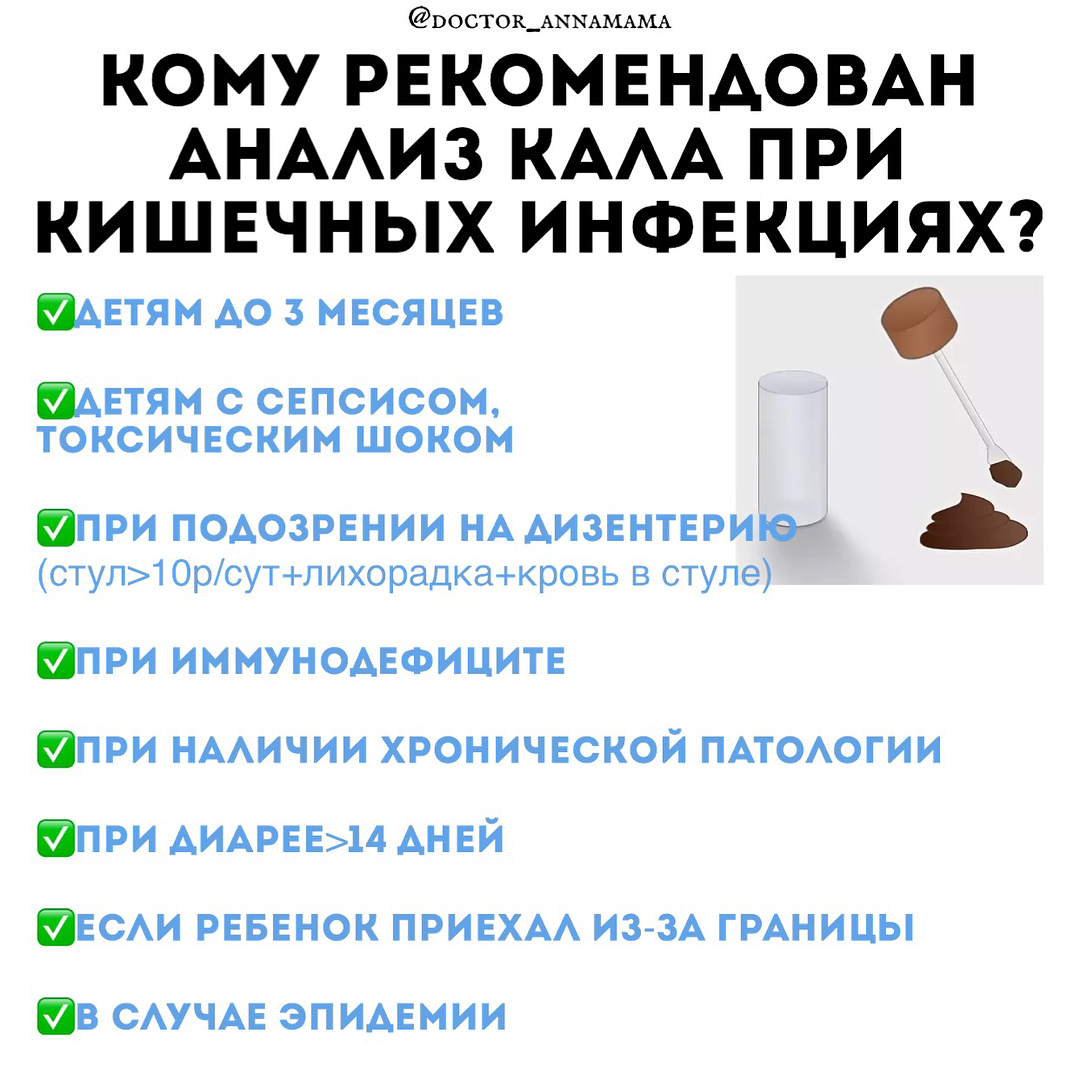

Кишечная инфекция схема лечения препараты

Кишечная инфекция аннамама